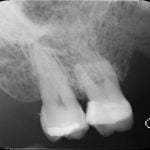

それでは、実際のCTスキャン画像をみながら説明いたします。以下は、根管治療時のCTスキャン画像です。左のレントゲン画像の歯のCT画像が右にあります。レントゲン画像では確認できなかった根尖病巣の黒い影(赤い矢印の先の影)が、いずれもはっきり確認できます。